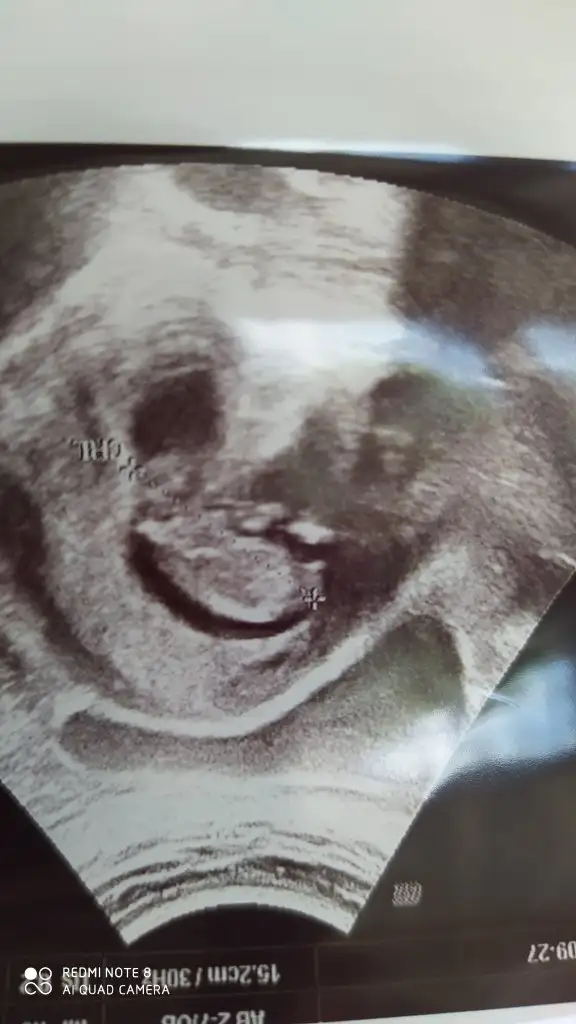

Merhaba bebeginizi gule gule buyutun insallah isteyen herkese versin rabbim bizlere de versinDoktor takibi ve testle takip ettim pik ve hafif silikken deneme oldu canım eşim takviye falan kullandı bende fitil kullandım karbonatlı su içtim birazcık beslenmeye özen göstermeye çalıştım aklına takılan olursa sor cevaplayayım. Rabbim hepinizs nasip etsin inşallah